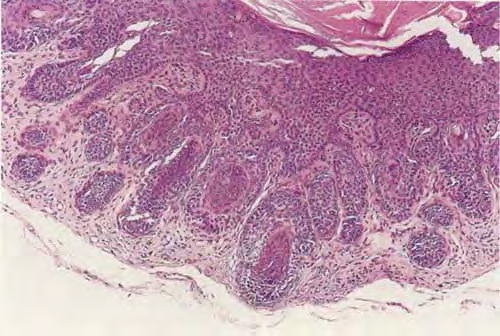

Trichofoliculoma =ورم جريبي شعري